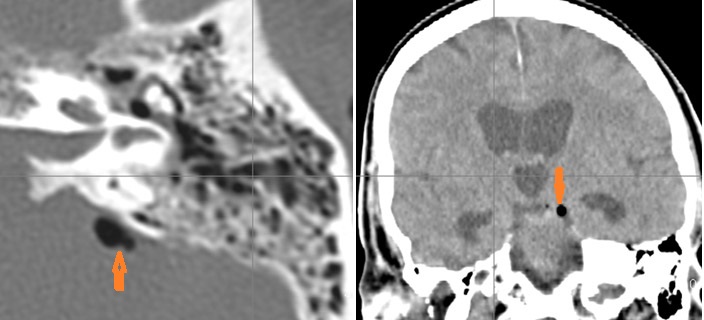

The petrous apex is abnormal.

The inner ear, in particular the lateral semicircular canal and the cochlea are eroded or otherwise abnormal.

There is dural reactive change along the floor of the middle cranial fossa or along the inner surfaces of the petrous portion of the temporal bone.

There is a subperiosteal, subdural or epidural abscess along the floor of the middle cranial fossa or along the inner surfaces of the petrous portion of the temporal bone.